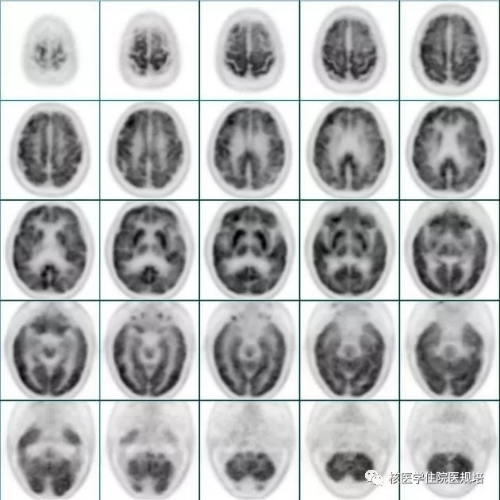

患者封闭视听15分钟后注射18F-FDG,随后在视听封闭状态下静卧休息;注射后1小时使用脑部专用检查程序行脑图像采集。经计算机重建处理后,获得三方位断层图像及SPM软件分析3D图,结果显示:大脑皮质形态正常,中线结构居中;双侧大脑半球皮质及神经核团FDG摄取不均匀性减低,以左侧额叶、顶叶及丘脑为著(图2-3);另可见全脑脑室、脑沟、脑池普遍增宽(图4)。

2

3

4

1.脑灰质及神经核团FDG代谢不均匀减低,以左侧额叶、顶叶及丘脑代谢减低为著,可符合皮质基底节变性表现

18F-FDG PET/CT显像反映的是脑组织葡萄糖代谢水平,不同疾病累及脑组织的部位不同,PET/CT显像会有其特征性的表现。脑部不对称性葡萄糖代谢改变对于CBD 的诊断和鉴别诊断具有重要临床意义,即严重受累肢体对侧的脑区存在明显葡萄糖代谢减低。虽然以往研究所报道的脑异常代谢区分布有所差异,但CBD患者总会出现皮质代谢减低,多见于严重受累肢体对侧的额叶、顶叶和丘脑,而约一半患者并不存在基底节代谢减低。本病例中的患者右侧肢体肌张力增高明显,FDG PET/CT显像显示左侧额叶、顶叶及丘脑代谢减低,与既往报道结果也一致[1],故可符合CBD表现,且提示该病变仅位于皮质,基底节并未受累。

神经退行性疾病在临床症状上表现或多或少相似,但是在脑FDG PET/CT影像中可能会出现其特征表现,这对临床鉴别诊断会有帮助。如PD表现为壳核、感觉运动皮质及小脑代谢相对稍高,余脑区代谢减低;MSA表现为双侧小脑、脑桥和壳核代谢减低;PSP表现双侧额叶、尾状核和中脑代谢减低;DLB以双侧枕叶代谢减低为著等[2](图5)。